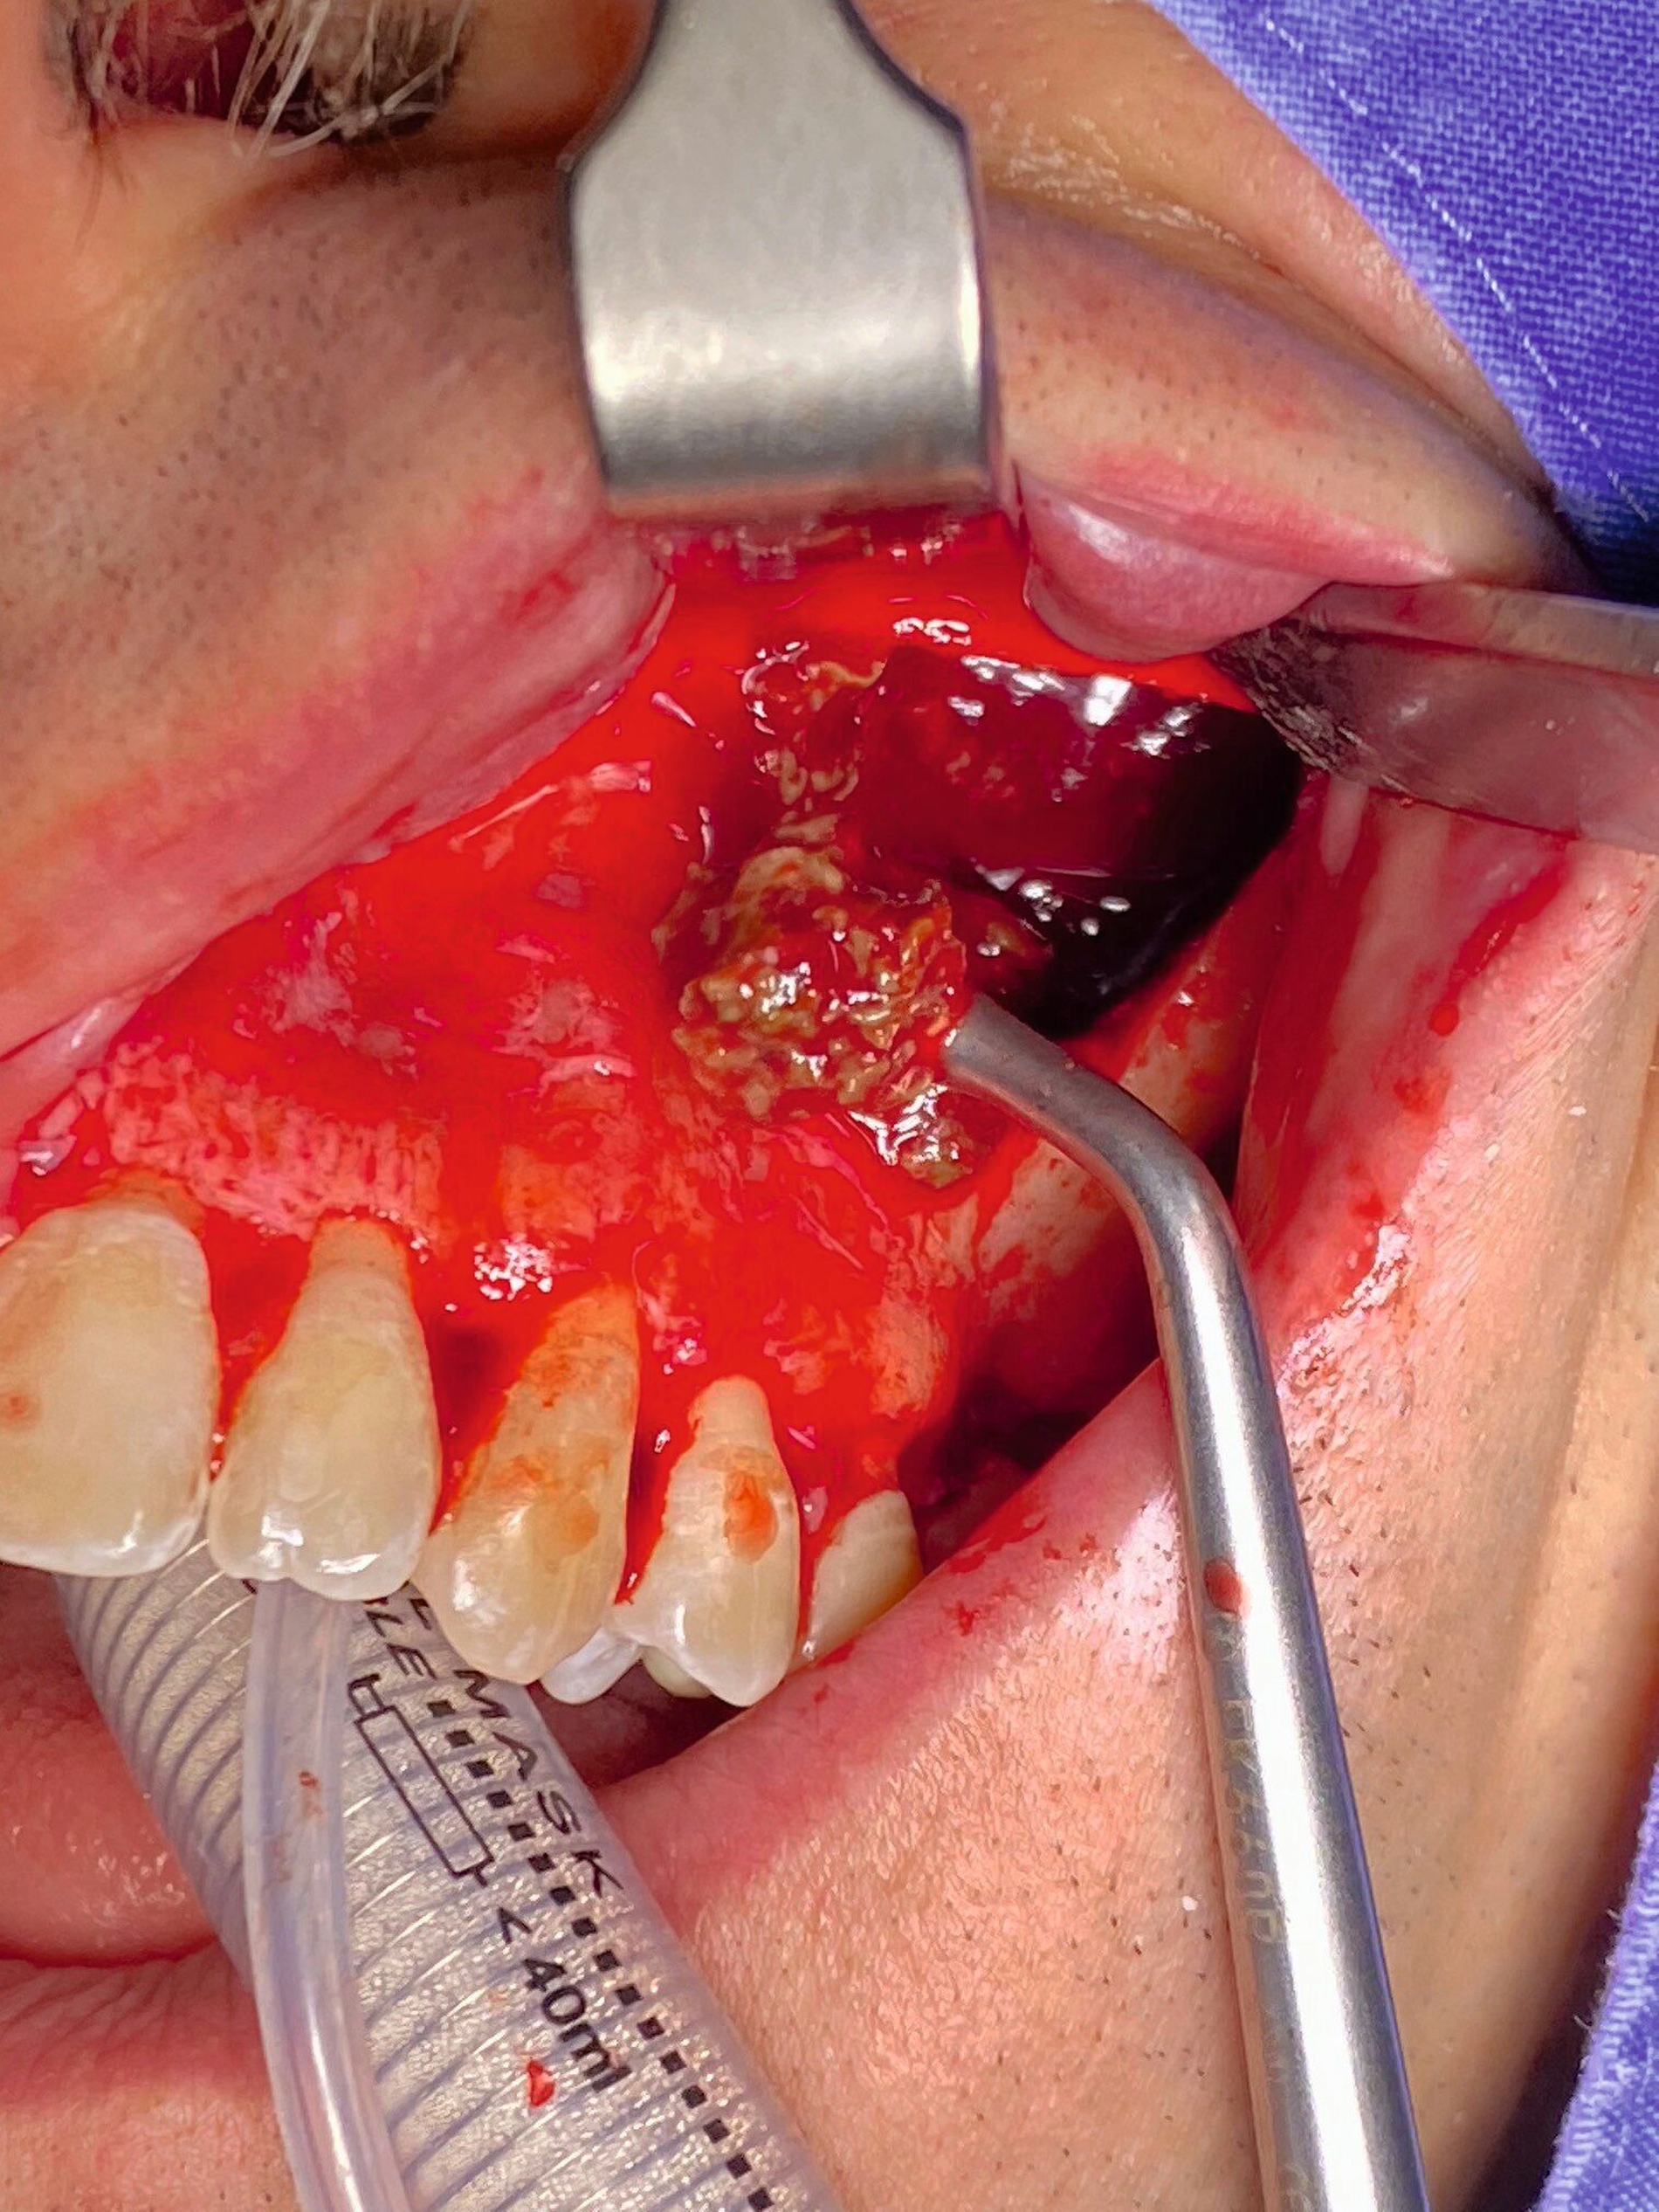

Die Therapie erfolgte in ambulanter Vollnarkose mittels Lindorf-Deckel-Technik. Nach marginaler Schnittführung und Darstellung der Kieferhöhlenvorderwand wurde mittels Piezosurgery ein knöcherner Deckel präpariert und der Sinus eröffnet (Abbildung 3). Es zeigten sich eine große Menge bröckeliges, schwarz verfärbtes Material sowie eine entzündlich veränderte Schleimhaut (Abbildung 4).

Zudem wurde ein Zahnkronenfragment geborgen (Abbildung 7). Die Kieferhöhle wurde unter Erhalt der auskleidenden Schleimhaut vollständig gereinigt und mit physiologischer Kochsalzlösung gespült. Zur postoperativen Spültherapie wurde transnasal ein Drainageröhrchen durch das Ostium naturale eingelegt (Abbildung 5). Auf ein Fenster zum unteren Nasengang wurde daher verzichtet. Der Knochendeckel wurde reponiert und mit resorbierbaren Nähten fixiert (Abbildung 6).